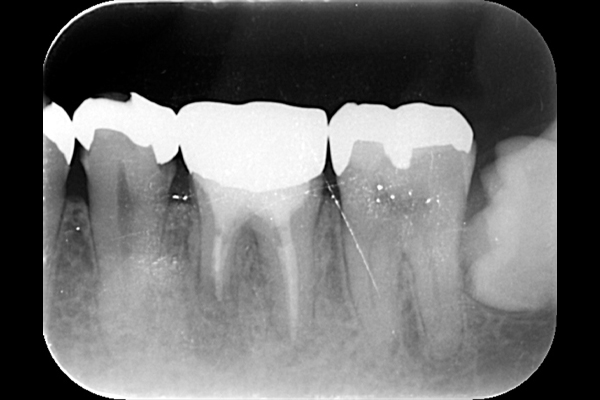

それは歯の先に枝分かれが多く存在し、そこにばい菌が入り込んで難治性となっているからです。ではその場合どうするのか?外科治療をします。その枝分かれの部分を切り落とすのです。今回はその前後のレントゲンの写真をお見せします。

| 根の中の薬が十分に充填されておらず、根の先が周りと比べて黒くなっており、炎症があると判断できます。 | 根の中にしっかりとお薬を緊密に充填しましたが、まだ根の先に黒くなっている部分があります。 |